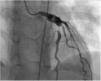

At five years of age, weighing 23.1 kg and measuring 116 cm, the patient was re-catheterized and progression of the previously documented lesions was noted. He was asymptomatic. Physical examination was unremarkable. Coronary angiography showed a CAA of the LAD measuring 17 mm×7 mm involving the first diagonal branch associated with a 90% post-aneurysmal stenosis (Figure 1), and a CAA of the RCA measuring 32 mm×6 mm.

Figure 1.

Coronary angiography showing coronary artery aneurysm of the anterior descending coronary artery measuring 17 mm×7 mm and involving the first diagonal branch, associated with 90% post-aneurysmal stenosis.